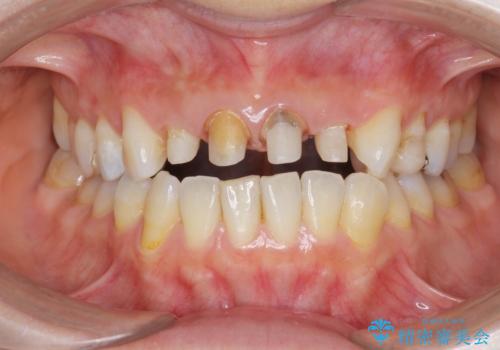

黒ずんだ見栄えの悪い前歯をきれいにしたい

- 「黒ずんで、見栄えの悪い前歯をきれいにしたい。」と、前歯のセラミック治療を希望され来院されました。

全て根管治療のすでになされている歯の変色で、オールセラミッククラウンによる審美性の改善を計画します。

- 52.8万円(ジルコニアクラウン×4・仮歯×4)費用は治療当時の料金となります